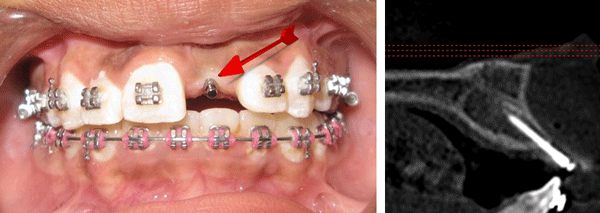

Case Study:

Here is a case for a girl 11 year-old with missing UL1. A Templant was placed with a same day retoration. Templant Age as of 2023;  8 years. Number of adjustment: One.